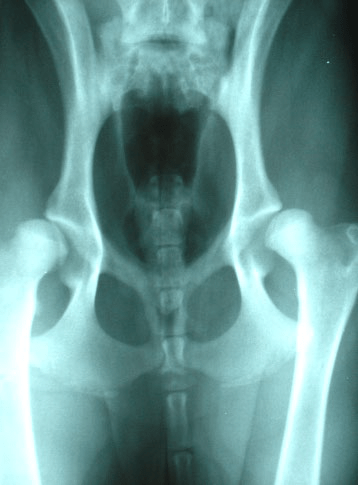

Schnauzern är en ras som inte har några signifikanta problem med höftlederna till skillnad från de som vissa större och tyngre raser har. Detta framgår av försäkringsbolagens statistik och den enkät som genomfördes av vår avelskommitté inför den senaste RAS (Rasspecifik Avels strategi). Detta motsäger nyttan av HD-röntgen så varför ska vi då röntga och varför började vi med det?

Ett skäl som man brukar hävda är att det krävs för internationellt avelsutbyte och så är det till exempel i Tyskland. Det internationella avelsutbytet är vi beroende av då vår ras är liten med ca 160 registreringar per år och avelsbasen därmed begränsad. Detta förklarar inte varför jag som enskild hundägare ska behöva röntga.Man brukar prata om att avelsdjuren ska ha ”fria” höftleder. Med detta menas vanligen A- eller B-status vid röntgenavläsning. C kan också accepteras. Detta är dock inte hela sanningen. Uppfödaren har också behov av att veta HD-statusen på avkommor, syskon, föräldrar etcetera.

Rasens fortlevnad och utveckling med god fysisk och mental hälsa är dock inte enbart upp till uppfödarna utan även schnauzerägarna har del i detta. Skulle min hund ha dåliga höftleder, finns det goda möjligheter att hunden kan få ett bra liv utan smärta eller hinder genom rätt träning och hantering. Här har den enskilde hundägaren också ett ansvar genom att valpen ges så bra förutsättningar som möjligt. När valparna föds har de inga fel på höftlederna, men de är inte färdigutvecklade. Såväl lårben som bäcken består mest av brosk, som är mjukt och kan deformeras och ge en felaktig höftled.